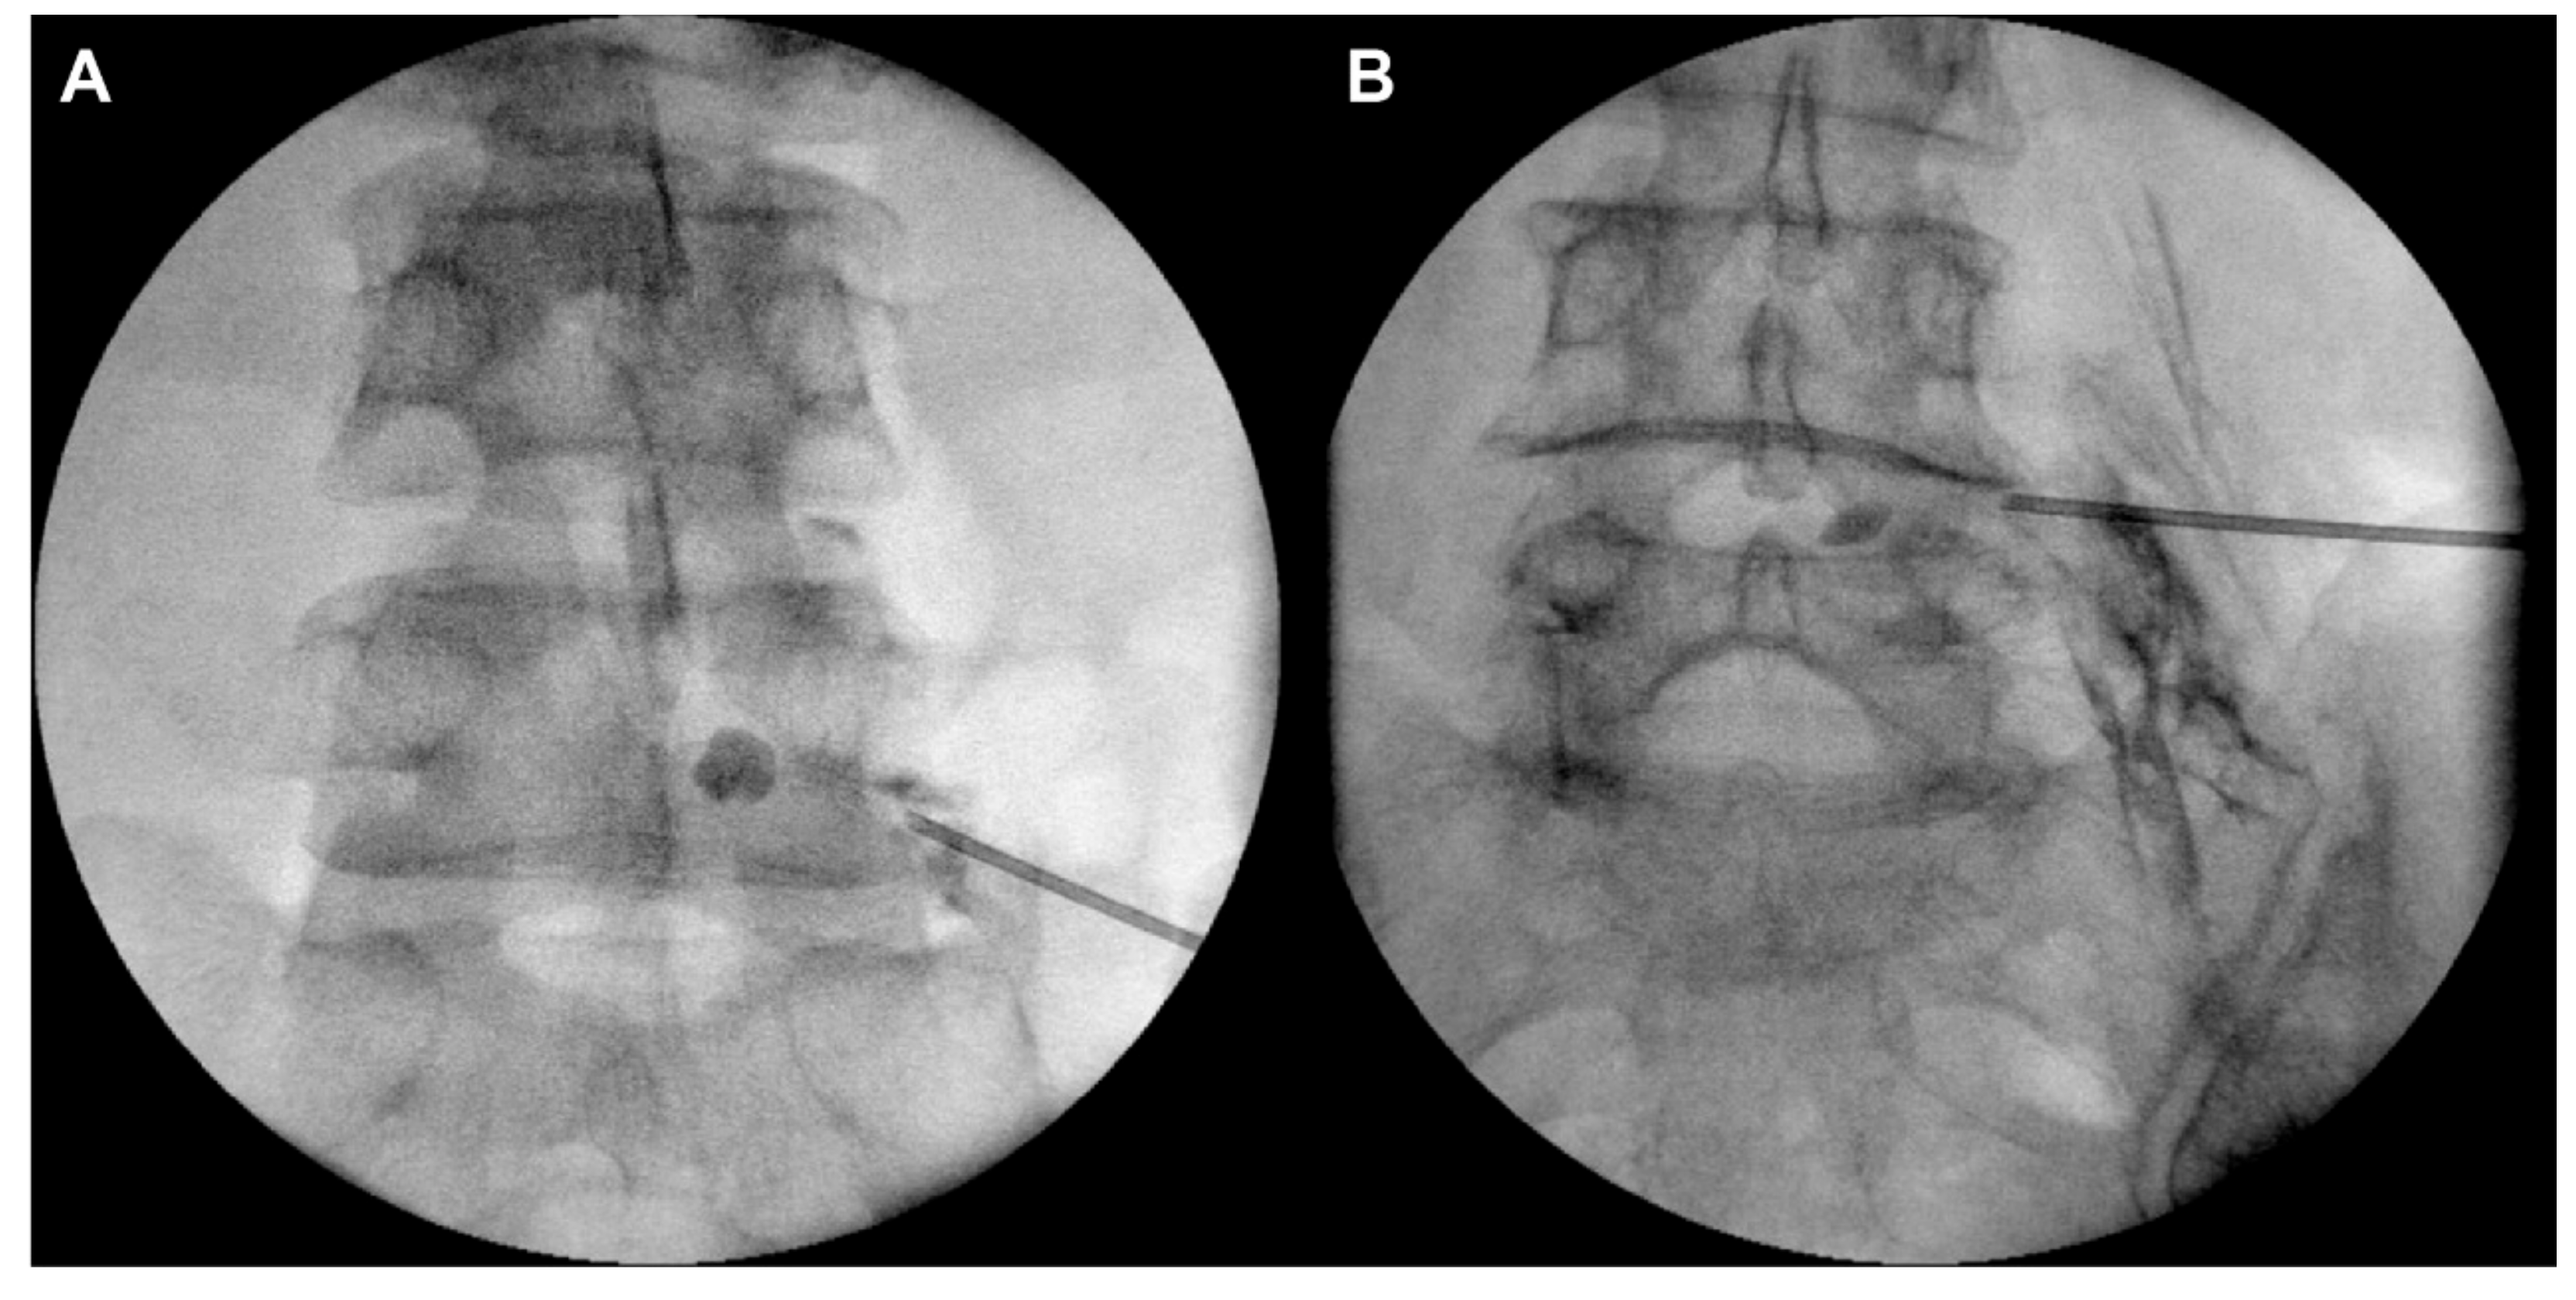

2.3. Percutaneous Transforaminal Epidural Adhesiolysis Using an Inflatable Balloon Catheter